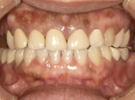

歯がこのままではダメだと思い、一念発起された50代女性の方です。

もちろん治療期間が長期にかかることも、治療費が高額になることも、外科的な手術が何度か必要であることなど、

インプラント治療と咬み合わせ治療のほぼ全てを大名歯科ホームページで予め知っていただいた上で決心され来院されたそうです。

インプラント治療は顎骨が乏しかったため、増骨手術も併用しなければならない難症例でした。

治療期間中は残存歯数が少ない上に、丈夫でないため生活に不自由な点がでました。

さらに咬み合わせが安定しにくい症例のため、プラスチック仮歯がよく壊れたり、外れたりして、修理に来院していただくなど大変な苦労とご迷惑をおかけしました。

審美性(見た目)は十分回復できたと思っており、患者さんも大変満足されています。

食事は当然のことかもしれませんが、よく咬めるようになったそうです。

咬み合わせ治療は非常に難しいため、これで十分かどうか分かりませんが現在もこのまま定期的なメインテナンス中です。